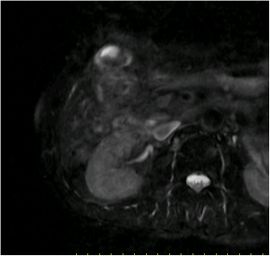

CT検査にて胆嚢底部に限局性に壁肥厚を認め、精査の結果、悪性病変疑いと診断。腹腔鏡下胆嚢摘出術を施行した。病理結果は胆嚢がんであった。

MRI画像